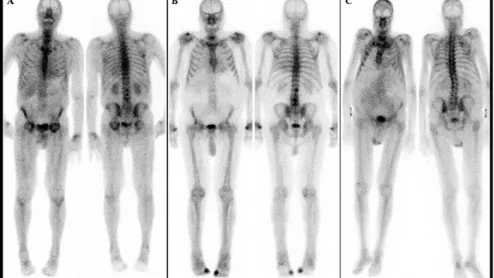

cardiac amyloidosis on bone scan

The two vendors involved say supplies of PYP and HDP could be disrupted for months.